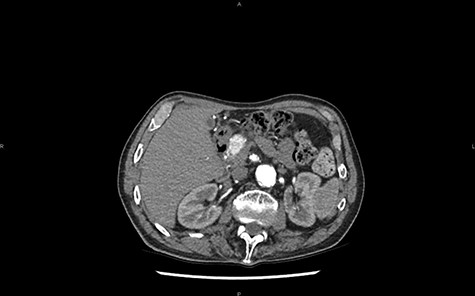

Magnetic resonance imaging (MRI) confirms the hypervascularized and atypical character of this pancreatic tumor (Figs 2 and 3). Moreover, one hepatic lesion with the same characteristics is highlighted.

MRI in axial section, phase T1 + gadolinium: visualization of a structure with hypersignal at the level of the head of the pancreas.